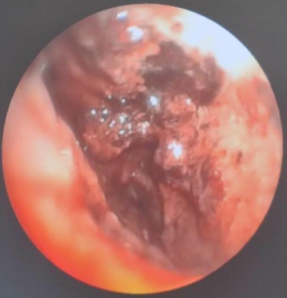

患者中年女性,农民,因“呼吸困难、咯血7天”于2023年9月7日入住我科。入院前7天,患者于我院内分泌科住院治疗时出现呼吸困难,伴咳嗽、咳痰,咳白色黏痰,痰中带血,呈鲜红色,病程中咯血量逐渐增多,每天10~20 ml,咯暗红色血性液体,伴发热,体温最高38.8℃。完善相关检查:血图分析提示白细胞计数15.21×109/L,CRP>200 mg/L,肺动脉CTA提示(图1):①肺动脉栓塞,累及左肺上叶前段、舌段,左肺下叶前内基底段局部受累可能;②左肺炎症较前明显增多。予哌拉西林舒巴坦、亚胺培南西司他丁、卡泊芬净抗感染,卡络磺、云南白药、矛头蝮蛇血凝酶止血后,咯血症状较前好转,余症状无明显改善,为求进一步诊疗于我科就诊。

图1  患者入院前肺动脉CTA